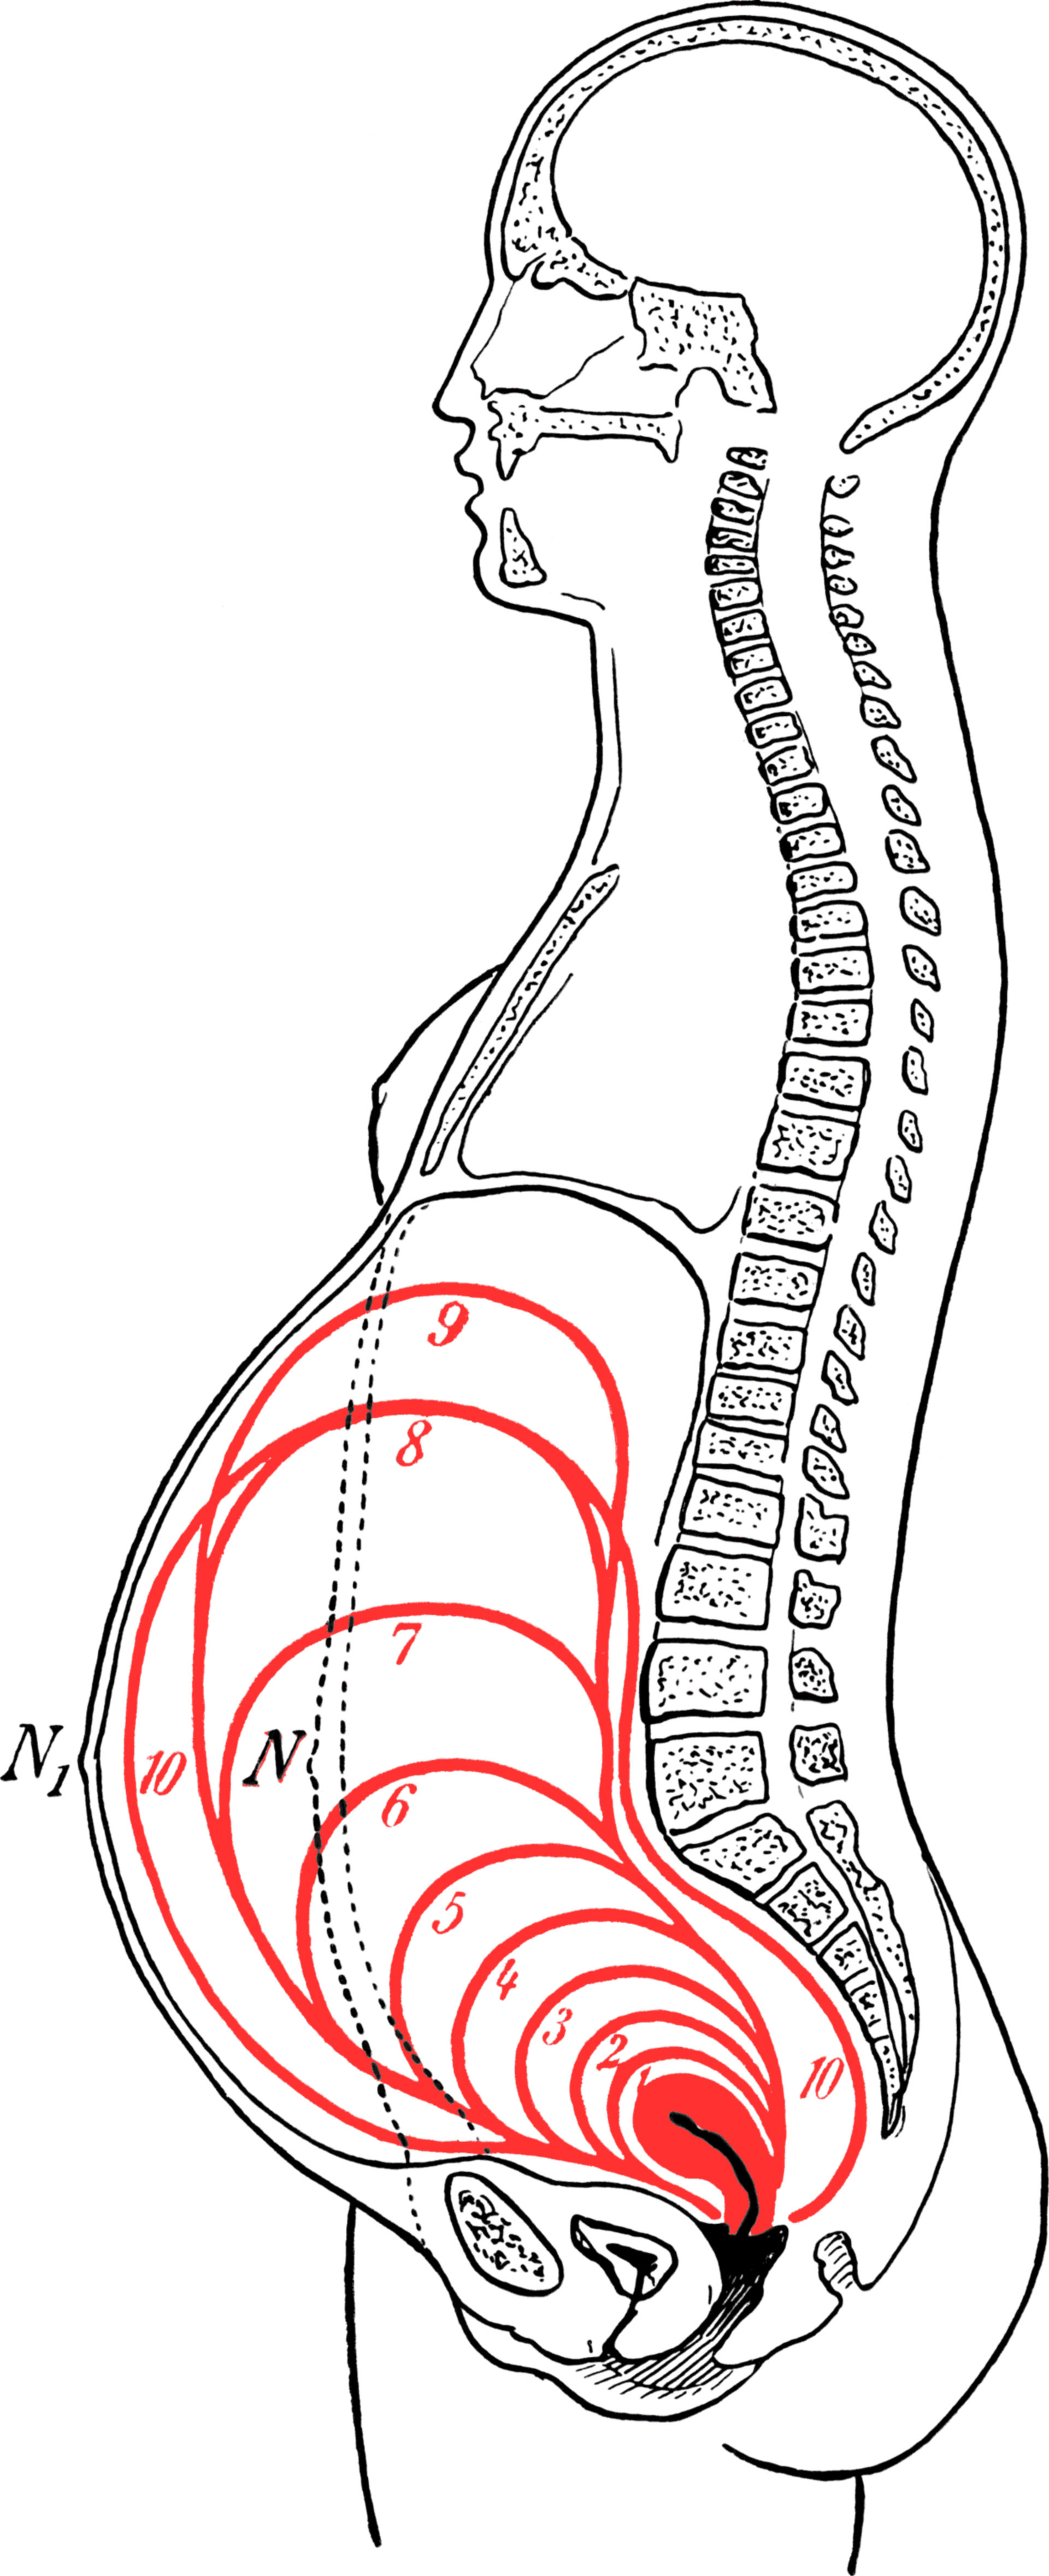

https://dccdn.de/www.doccheck.com/data/99/ju/rr/kh/eu/f6/grossedergebarmutterindeneinzelnemonatenderschwangerschaft_lg.jpg

Pregnant Uterus

Pregnant Uterus

Uterine Height Chart A Visual Reference Of Charts Chart Master

Uterus Pregnancy Length

Uterus Pregnancy Length